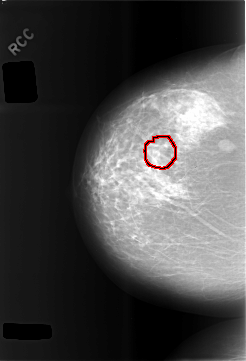

C_0479_1.RIGHT_CC

RIGHT_CC LINES 5768 PIXELS_PER_LINE 3936 BITS_PER_PIXEL 12 RESOLUTION 50 OVERLAY

FILE: C_0479_1.RIGHT_CC.OVERLAY

TOTAL_ABNORMALITIES 1

ABNORMALITY 1

LESION_TYPE MASS SHAPE OVAL MARGINS CIRCUMSCRIBED

ASSESSMENT 3

SUBTLETY 5

PATHOLOGY BENIGN

TOTAL_OUTLINES 1

BOUNDARY